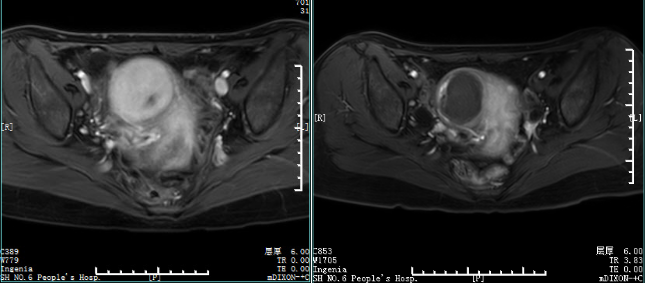

患者,女,31歲,子宮右側壁肌瘤,大小5.0*5.2*4.8cm,平素月經量大,有痛經,血常規(guī)(治療前):Hb 104g/L。HIFU治療五次,每次半小時。治療后1月患者自訴月經量減少1/3,半年后子宮肌瘤縮小至2.5*2.8*2.6mm,復查血常規(guī):Hb 145g/L。

子宮肌瘤 HIFU治療前MRI增強,治療后1月MRI增強。